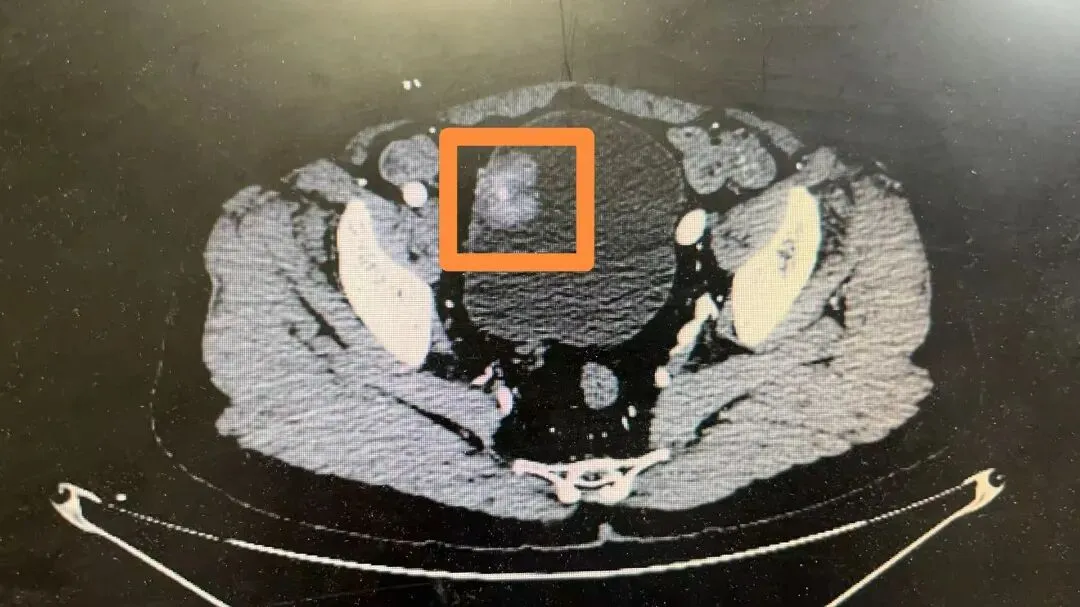

案例四:患者因“体检发现双附件包块一个月”入院。彩超示右附件区探及囊性团块,大小约71mmx55mm;左卵巢内见稍高回声,大小约16mmx15mm。行腹腔镜下双侧卵巢囊肿剔除术。术后病理结果显示:右卵巢浆液性囊腺瘤,左卵巢成熟性畸胎瘤。

术前CT